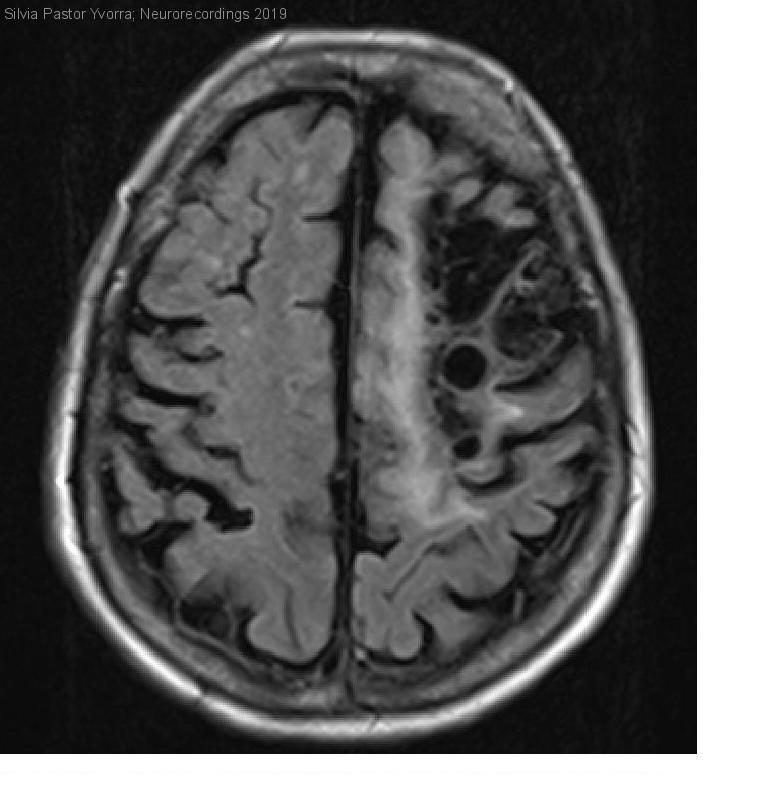

Mujer | 31 años

Diagnóstico final: Infarto cerebral en territorio de la arteria cerebral media izquierda de causa inhabitual. Epilepsia focal frontal izquierda

Paciente con infarto cerebral antiguo en territorio de arteria cerebral media izquierda (ACM-I) y epilepsia focal de etiología lesional, acude para estudio etiológico de sus patologías neurológicas. En la exploración se objetiva hipoestesia táctil protopática...